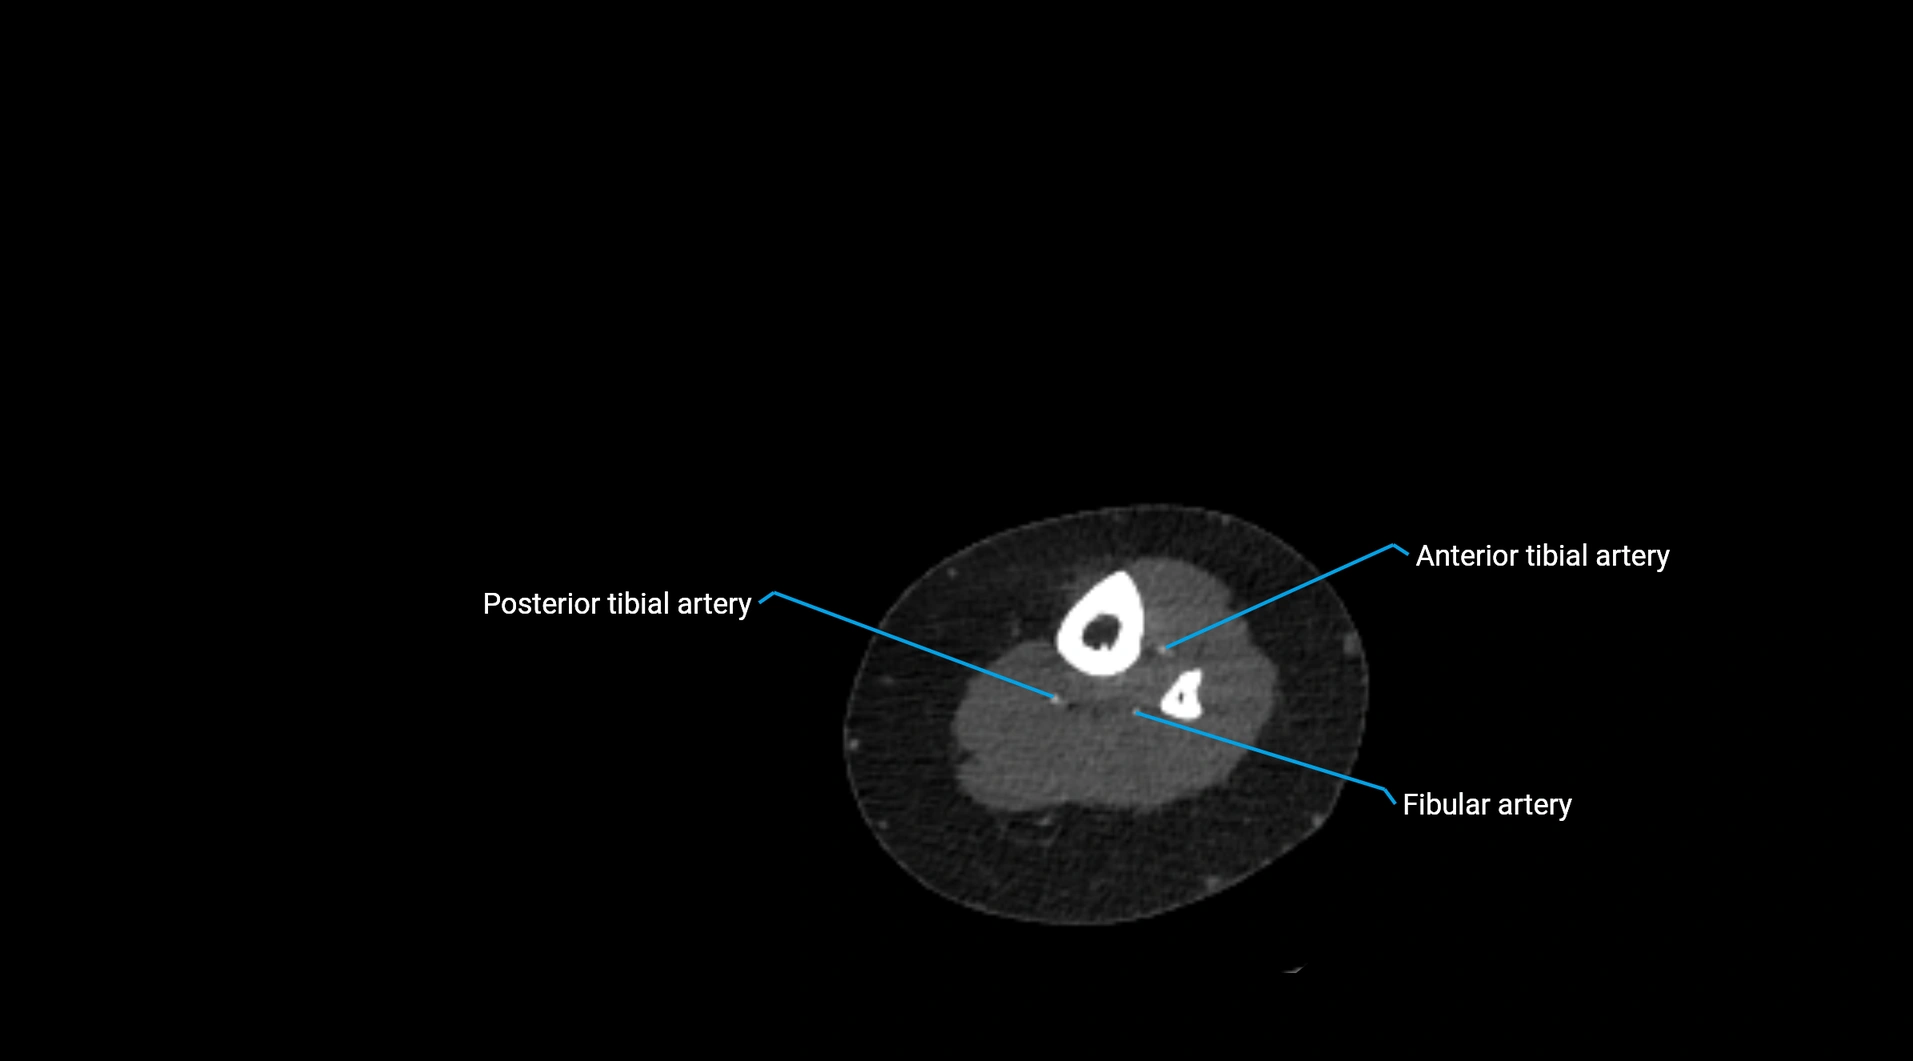

CT images

image

Contrast-enhanced CT (CTA):

• Gold standard for abdominal aortic imaging

• Provides excellent detail of lumen, wall, aneurysm, thrombus, and branch vessels

• Multiplanar and 3D reconstructions help in aneurysm measurement, stent graft planning, and dissection evaluation